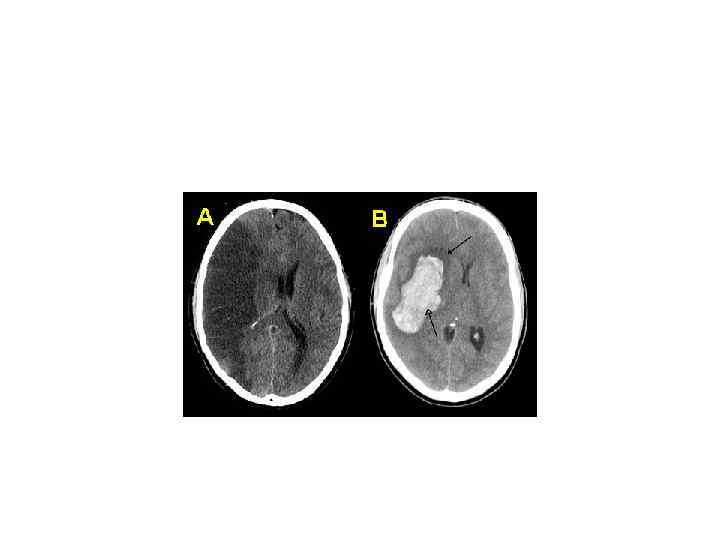

Относительная плотность Относительно дистиллированной воды: • Цельная кровь — 1, 050 -1, 060 • Эритроциты — 1, 090 • Плазма крови — 1, 025 -1, 034

Хаунсфилда